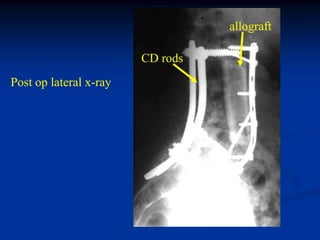

49 year male with recurrent chordoma sacrum

Wide resection entire                   CD rod

sacrum and recon with           L-5

CD rods and Steinman

pins prior to cementation

Steinman pins

CD rods

After cementation

cement sacrum

Post op x-ray

cement

L-4

L-5

Lateral view

cement coccyx

Case #224               Sagittal T-1 MRI

L-3

S-1

55 year male with chordoma lumbar spine

Resection L-4, L-5 and part of S-1

Resected vertebrae

Photomic

sacrum

Anterior recon with large bone allograft and plate

allograft

Post op lateral x-ray